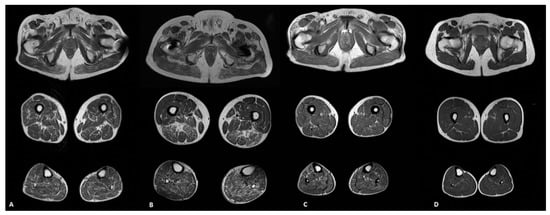

3. Results